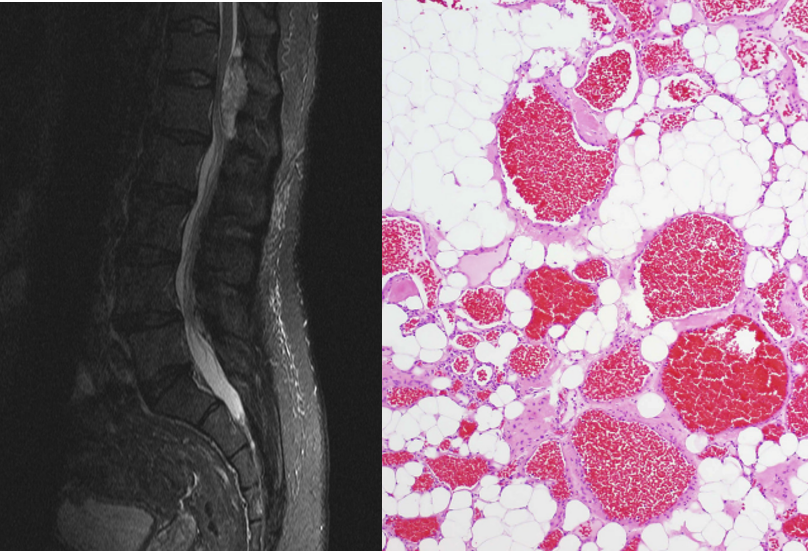

典型影像、病理学特征:MRI可见混合信号:脂肪、血管成分在同一区域内并存,与海绵状血管瘤相比为混杂信号且边界模糊欠规则(左)。病理成分相比含有较多脂肪细胞(右)。